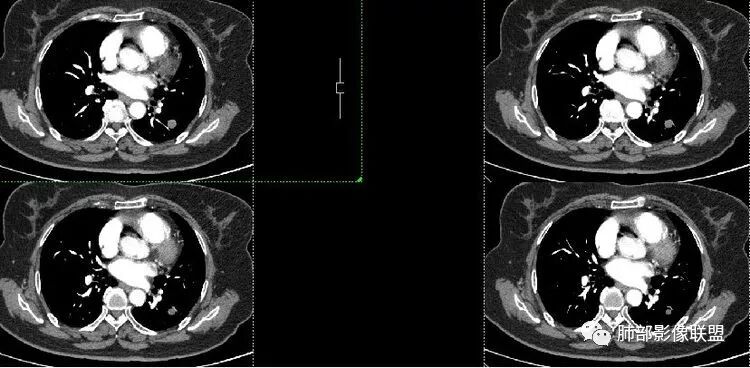

患者老年女性,体检发现左肺占位3天。有“高血压”病史。查体无阳性体征。胸部CT:左肺下叶背段类圆形实性结节,边缘清晰,边界光滑,未见毛刺、分叶、棘突等征象,与支气管关系不清,增强中度强化,可见贴边血管征、尾征。综合考虑良性病变,硬化性肺细胞瘤可能大,鉴别孤立纤维瘤、错构瘤。

患者老年女性,体检发现左肺占位3天。胸部CT:左肺下叶背段类圆形实性结节,边缘清晰,边界光滑,未见毛刺、分叶、棘突等征象,增强扫描中度延迟强化,局部与血管贴边生长。考虑良性病变,PSP可能大,炎性肉芽肿、错构瘤不排除。

血管贴边征一般是有前提的

孤立结节,类圆形,边缘光滑,周围干净

与支气管有关吗?好像显示不明显

与血管的关系?

局部稍推压变

对比同级别血管稍增粗

密度尚均匀

支持良性

PSP可能 错构瘤待排